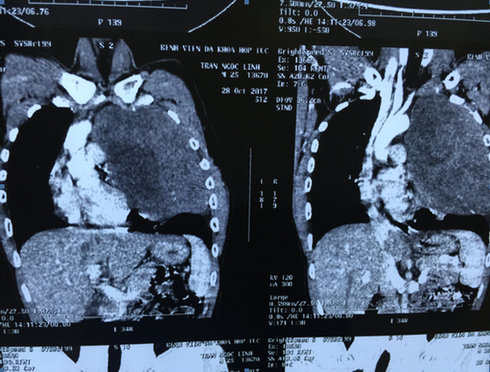

Bệnh nhân nam 25 tuổi, mắc khối u bất thường |

Tại bệnh viện K, các bác sĩ chẩn đoán bệnh nhân bị u thần kinh trung thất trên trái. Khối u đường kính lớn 20 x 16 cm, hoại tử một số vùng,chiếm toàn bộ khoang lồng ngực trái, kéo dài từ nền cổ tới gần sát cơ hoành, đè đẩy tim và các mạch máu lớn, làm xẹp nhĩ trái. Cực trên khối u chèn ép vào bó mạch thần kinh cánh tay, cực dưới đè đẩy xẹp gần như toàn bộ phổi trái. Kết quả sinh thiết kim chẩn đoán giải phẫu bệnh kết luận u xơ thần kinh lành tính.

Kết quả chụp phim |